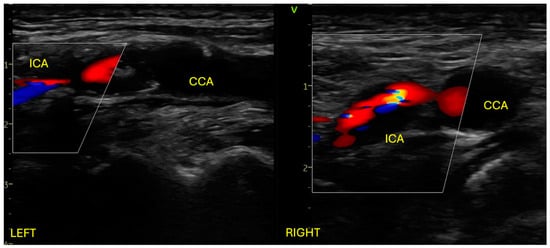

We present the case of a 64-year-old male patient with a recent history (one month) of left ACA-MCA and MCA-PCA ischemic strokes with right hemiparesis, documented on cerebral CT. A chronic frontal right ischemic lesion was also documented. Neurological examination on admission revealed right minor central facial palsy, 3/5 MRC right hemiparesis, and mild right hemihypoesthesia, consistent with an NIHSS score of 4. Past medical history revealed ischemic heart disease, with severe stenosis at the proximal level of the anterior descending artery, treated with balloon angioplasty and two drug-eluting stents 6 months before admission. Also, the patient was diagnosed with hypertension, type II diabetes, and obesity. The patient was on dual antiplatelet therapy with Aspirin and Clopidogrel. At admission, he was stable, with a 110–120 mmHg systolic blood pressure, a 95 bpm regular pulse, and a 98% peripheral oxygen saturation. He had almost complete resolution of the right hemiparesis with the rest of the clinical examination within normal limits. The blood test revealed hyperlipidemia. The EKG showed normal sinus rhythm, without any ST-T changes, and the chest XR was without any pathological findings. Transthoracic echocardiography showed normal biventricular function, no significant valvular pathology, and no pericardial effusion. Arterial Doppler ultrasound of the carotid arteries revealed 90–95% stenosis at the level of the left common carotid artery bifurcation, extending to the internal carotid artery, and 85–90% stenosis at the level of the right common carotid artery bifurcation, extending at the level of the internal carotid artery. The atheromatous plaques responsible for the severe bilateral stenosis were both of mixt echogenicity (Figure 1).

Figure 1.

Arterial Doppler ultrasound of the carotid system showing bilateral severe stenosis at the level of common carotid artery bifurcation extending at the level of the internal carotid artery. ICA: internal carotid artery; CCA: common carotid artery.